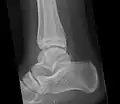

Os trigonum

The os trigonum or accessory talus represents a failure of fusion of the lateral tubercle of the posterior process of the talus bone. Is estimated to be present in 7–25% of adults.[17] It can be mistaken for an avulsion fracture of lateral tubercle of talus (Shepherd fracture) or a fracture of the Stieda process. In most cases, Os Trigonum will go unnoticed, but with some ankle injuries it can get trapped between the heel and ankle bones which irritates the surrounding structures, leading to Os Trigonum Syndrome.[21]